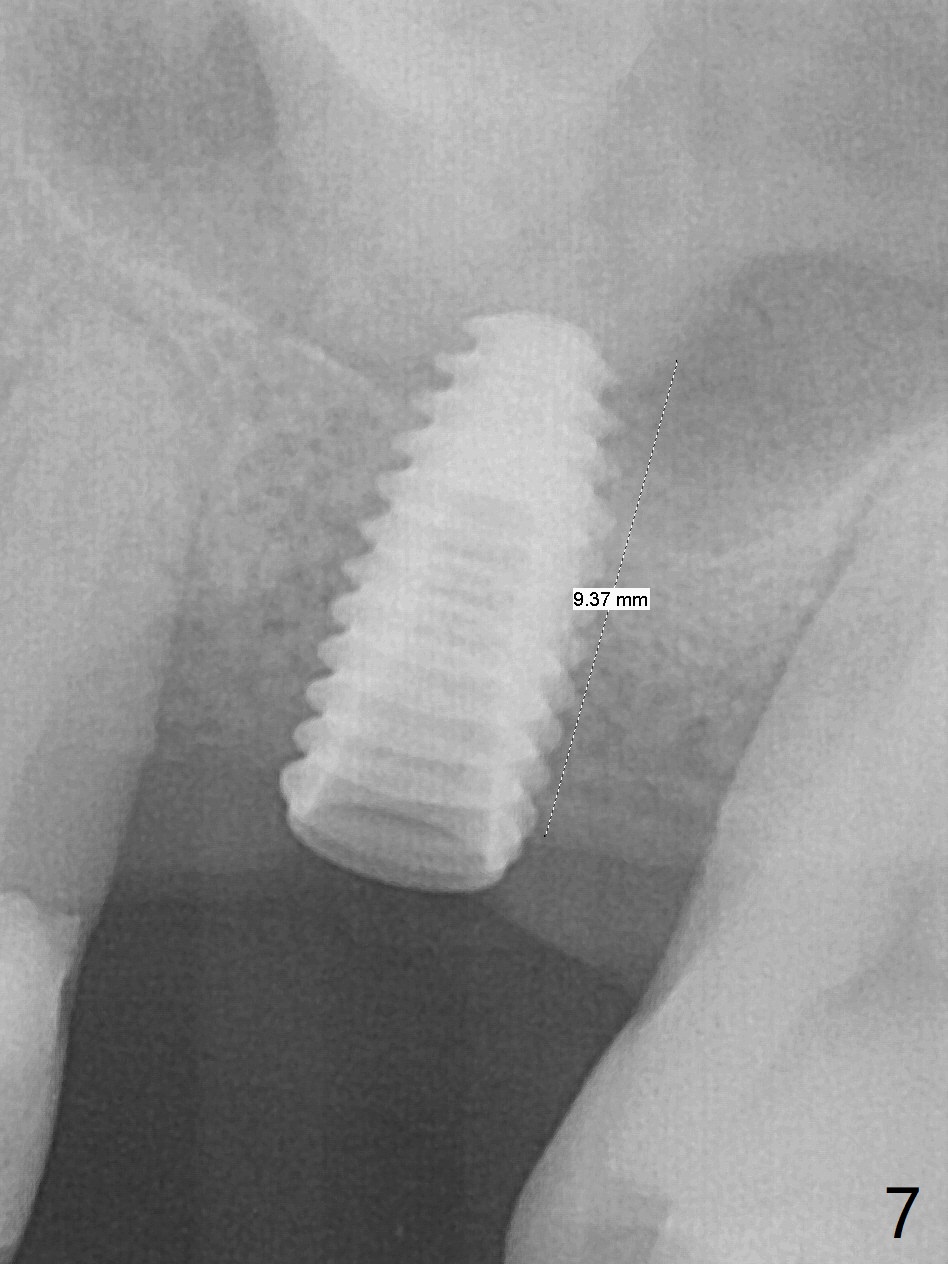

Trajectory of sinus lift without guide at #14 is off (Fig.1 (Magic Sinus Lifter (L) for 9 mm (gingival level)) and needs to be corrected (Fig.2 long line) by re-using 4.8 mm Magic Drill. Following placement of PRF membrane and Demineralized Cortical Allograft (.125-.850 mm) for sinus lift (Fig.3 black dashed line), a 4x10 mm dummy implant is placed with off trajectory. The latter will be fixed by using Lindmann bur to remove the bone distal (Fig.4). The result is less satisfactory with placement of 4.5x10 mm dummy implant (Fig.5). It appears necessary to initiate a new osteotomy (Fig.6 long black line). In fact the result is appealing (Fig.7). The final implant (5x7.3 mm) seems to be placed ideally shown by PA (Fig.8) and BW (Fig.9). Immediately postop CT demonstrates distal defect (Fig.10 *;3-D) and supracrestal placement palatal (Fig.11 P; coronal section). More allograft is then placed in these 2 areas. In all, it is difficult to establish a correct osteotomy without guide. The patient return for uncover 3.5 months postop, although there is a small hole in the middle of the incision (Fig.12). The crown/abutment becomes loose less than 1 month post cementation when the patient chews something tough. It is more related to the unfavorable implant/crown ratio. It is loose again 2 months later. Screw driver is buried inside the abutment with plumber tape. When it is loose for the 3rd time 13 months post cementation, the existing screw driver with a created slot (for retention) is buried without plumber tape after retorque at 35 Ncm (Fig.13). A tissue-level implant should have been used.